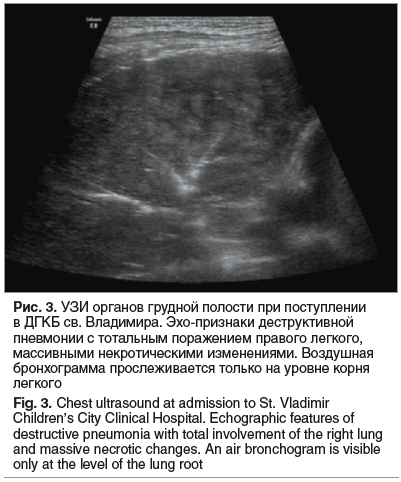

30.05.2024 (8-е сутки заболевания) — при УЗИ ОГП верхняя и средняя доли легкого консолидированы, неструктурны, с чередованием участков понижения и повышения эхогенности без четких контуров. Воздух прослеживается только в проекции корня легкого. Сосудистый рисунок резко обеднен. Констатированы массивные некротические изменения верхней и средней долей правого легкого (рис. 3). 31.05.2024 (9-е сутки заболевания) — мальчик в стабильно тяжелом состоянии переведен в отделение торакальной хирургии, где было продолжено проведение дренирования плевральной полости, санационные бронхоскопии. К 03.06.2024 (12-е сутки заболевания) по данным УЗИ ОГП на фоне безвоздушной ткани правого легкого в задних отделах появились множественные неправильной формы включения газа — дренированные зоны некроза легочной паренхимы. В передневерхней части легкого трансбронхиальное дренирование участков некроза отсутствовало. Справа визуализировались эхопризнаки пневмофибриноторакса. В этот период состояние ребенка оставалось тяжелым, начинающееся дренирование очагов деструкции сопровождалось подъемом температуры до 39,5 °С, повторным повышением уровней лейкоцитов (25,97×109/л), СРБ (236,91 мг/л), D-димера (10 799 нг/мл). Кроме того, отмечалось увеличение уровня ЛДГ (430,3 Ед/л при норме 110–295 Ед/л) как маркера повреждения тканей. В то же время уровень ПКТ продолжал снижаться (1,04 нг/мл). При МСКТ определялась тотальная консолидация верхней доли правого легкого, сегментарные бронхи прослеживались фрагментарно, визуализировались разнокалиберные воздушные полости от 1 до 9 мм, некоторые из них были сливными. Отмечена негомогенная консолидация средней и нижних долей. В средней доле выявлена полость с пенистым содержимым 29×31×9 мм, сообщающаяся с плевральной полостью (рис. 4).